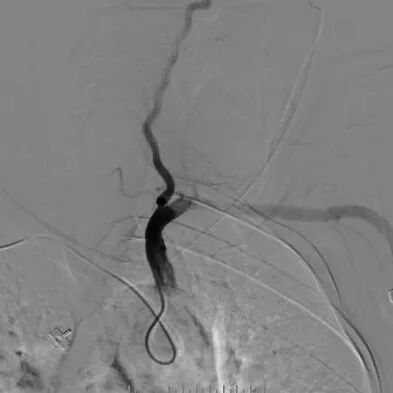

手术过程

-- 右侧桡动脉穿刺置入7F 泰尔茂薄壁鞘,波科7F0.081导引导管同轴5F 125cm SimmonsII导管在0.035导丝引导下引至左侧颈总动脉。

-- 路途引导下,FilterWire EZ保护伞顺利通过狭窄段至左侧颈内动脉岩骨水平段,顺利释放保护伞

--沿保护伞导丝引入波科4mm*30mm-Sterling球囊跨狭窄段扩张后,交换9mm*40mm-Wallstent支架经波科7F导引导管顺利到达狭窄段,跨狭窄段缓慢平稳释放。

-- 支架释放后残余狭窄稍高,再次交换引入波科4mm*30mm-Sterling球囊行支架内后扩张,使用5F 125cm多功能回收保护伞,复查造影示狭窄明显改善,前向血流通畅。